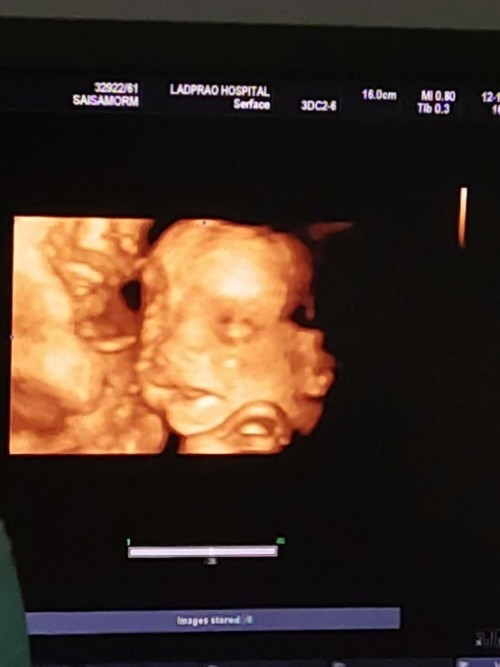

26+5w ลูกสาวค่ะ

Post reply image